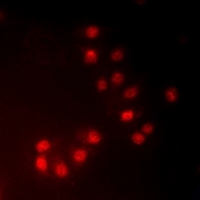

分类: 科研抗体货号: P41264别名: CREB2; CREBP1;应用: WB,IHC,IF反应种属: Human,Mouse,Rat